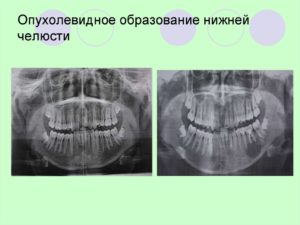

Ортопантомограммма пациента с остеобластомой нижней челюсти.